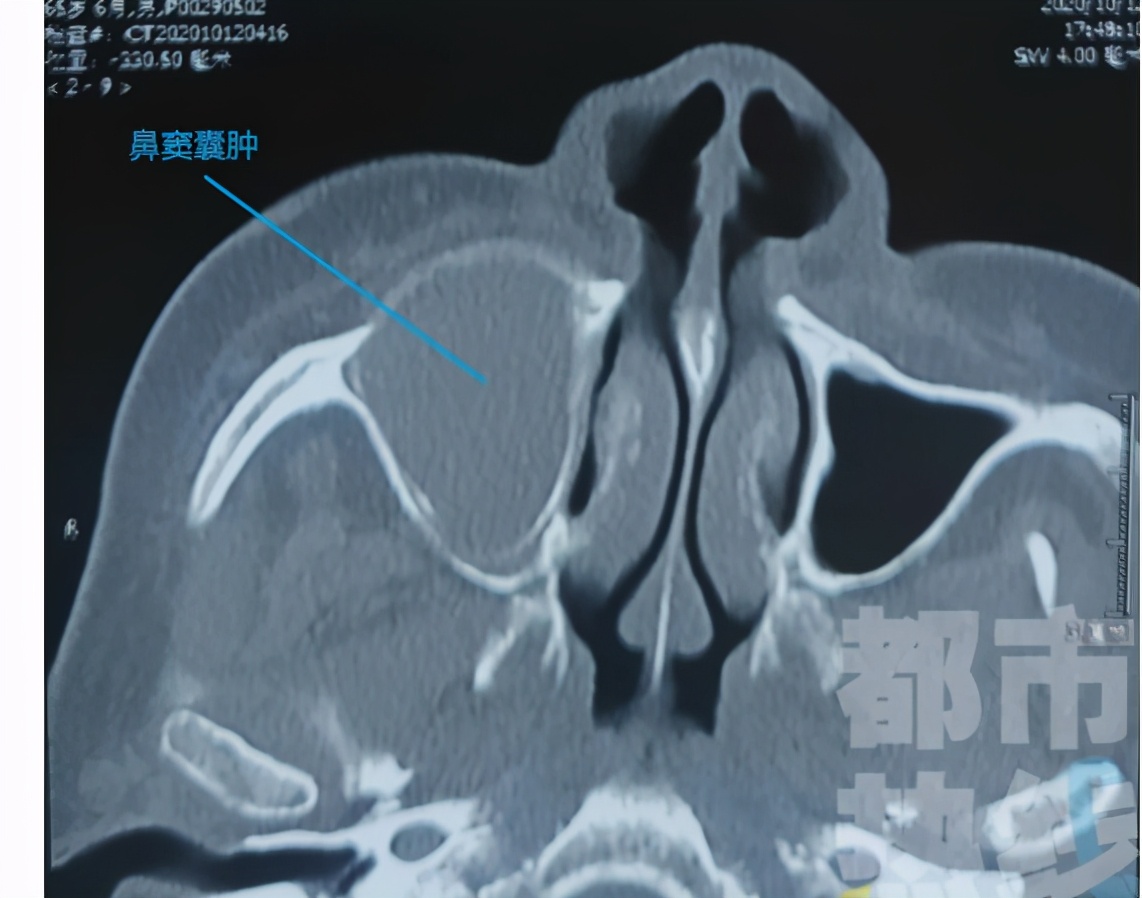

就上周吧,老朱在陕西都市快报上看到一则新闻,六十多岁的老刘从三年前开始就觉得自己的脸颊就有隐隐的胀痛却没注意,直到最近疼痛愈加明显,才赶紧去到口腔科检查。这一查不得了,拍片之后发现其实上颌窦里长了一个囊肿,而这囊肿里,竟有一颗异位的牙齿——原来,老刘得了鼻窦含牙囊肿。

鼻窦囊肿是指那些原发于鼻窦或者来源于牙或牙根并向上颌窦内发展的囊性肿物,一般属于耳鼻喉科。有朋友说,朱医生你不是口腔科吗,对这也有研究?那可不,毕竟容易挂错科。今天我们要聊的是上颌窦牙源性囊肿,这种囊肿一般是有上排牙发育障碍或者产生了病变导致的,牙齿突入上颌窦内变成了囊肿。像上文提到的老刘,主要是因为曾遭遇过外伤。

牙源性囊肿可以分为含牙囊肿,也就是老刘那种,一般在中青年之间产生的比较多,所含牙为未萌出的恒牙或额外牙。停留在牙槽骨中的未萌出恒牙可刺激造釉细胞,使呈增殖性变并产生分泌物而形成囊肿。牙釉质被包围在囊内,囊肿包膜为纤维组织构成,内膜为鳞状上皮。囊腔内含黄色或棕色液体;还有牙根囊肿,通常好发于老年人,为牙根感染,牙髓坏死,由牙根尖肉芽肿退行性变形成,他们都需要摘除囊肿然后处理病牙。比如老刘掉的半口牙,还得是让牙医给他再种上。